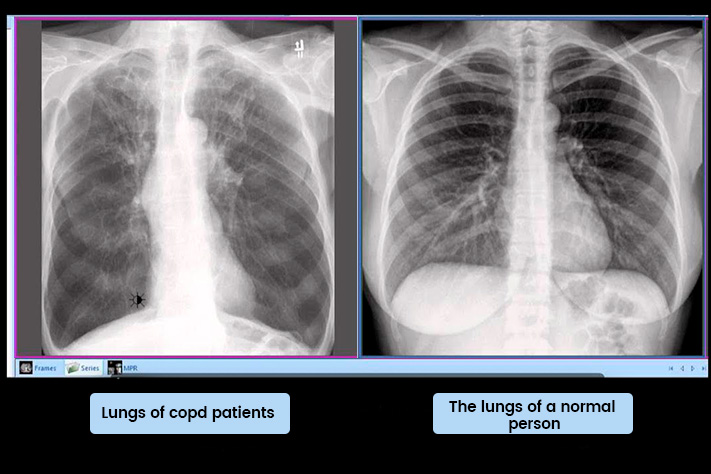

Check yourself! How worse are your lung cells and how high is the risk of an early death!

The most common cause of death is lung cancer, and the main cause of lung cancer is nicotine. It is the most dangerous substance in the world. This substance kills more people than alcohol and drugs combined. In 94% of cases, nicotine causes death in people under the age of 70.

It is much more dangerous that nicotine stimulates the nerves, causing bronchoconstriction and emphysema. Pathological processes occur in internal organs, which in turn lead to chronic diseases First there is emphysema, then there is chronic bronchitis, and some time later there is also stenosis of the bronchi. What usually leads to a drastic deterioration of human health. Most often this process is triggered by nicotine.

This substance enters the alveolar cells. At first, a small piece (20-25 years old) is stimulated, and then a larger and larger area of the lung is affected (25-40 years old), and the alveolar walls gradually become weaker and the elastic fibers deteriorate, consequently, at the age of 40 years, nicotine deactivates the alveoli by almost half. But even that is not so dangerous!

It is much more dangerous that nicotine stimulates the nerves, causing bronchoconstriction and emphysema. Pathological processes occur in internal organs, which in turn lead to chronic diseases.

First there is emphysema, then there is chronic bronchitis, and some time later there is also stenosis of the bronchi. What usually leads to a drastic deterioration of human health. Most often this process is triggered by nicotine.

Instead of 120 years (that's what human body organs are designed for), some don't even live past 70! Especially people who already have COPD at the age of 40-50. By the way, this is one of the most obvious symptoms of the loss of elasticity of the bronchial walls.

By the age of 50, cells throughout the lung become inflammed and destroyed. The more deactivated the cells are, the more chronic diseases you have and the faster the aging processes run!